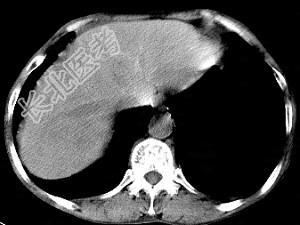

- 单项选择题男,40岁有血吸虫感染史, 腹胀不适,食欲减退, CT扫描所见如图,最可能的诊断是 ( )

A、肝炎后肝硬化

B、血吸虫后肝硬化

C、酒精性肝硬化

D、胆汁性肝硬化

E、脂肪肝